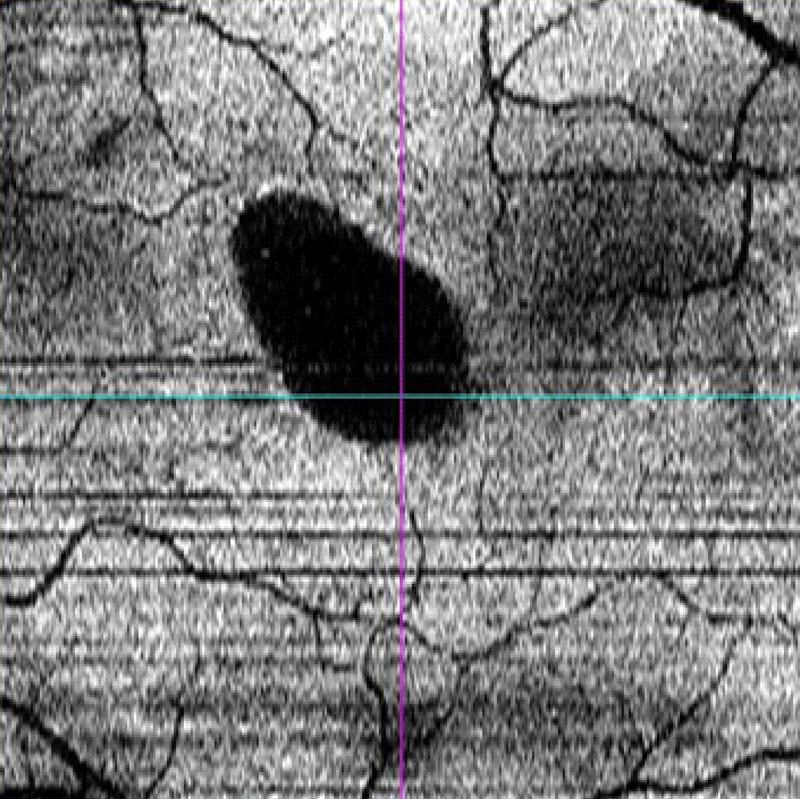

Estudio en face

El estudio

en face permite obtener una idea más clara del desprendimiento de la retina neurosensorial y de las alteraciones en el epitelio pigmentario de la retina (

Figura 6). Se han descrito la presencia de puntos hiperreflectivos en el epitelio pigmentario de la retina y cavitaciones en la coroides

7, aunque hasta la fecha no se conocen las implicaciones que pueden tener tales hallazgos. Con el desarrollo de OCT de muy alta resolución, el estudio en face puede ayudar a la valoración de la red vascular coroidea; por su alta definición puede sustituir a la angiografía y facilitar el diagnóstico diferencial con algunas formas de degeneración macular asociada a la edad

8.

Figura 6. Estudio en face de un paciente con coroidorretinopatía serosa central aguda. Se delimita con facilidad el desprendimiento neurosensorial.